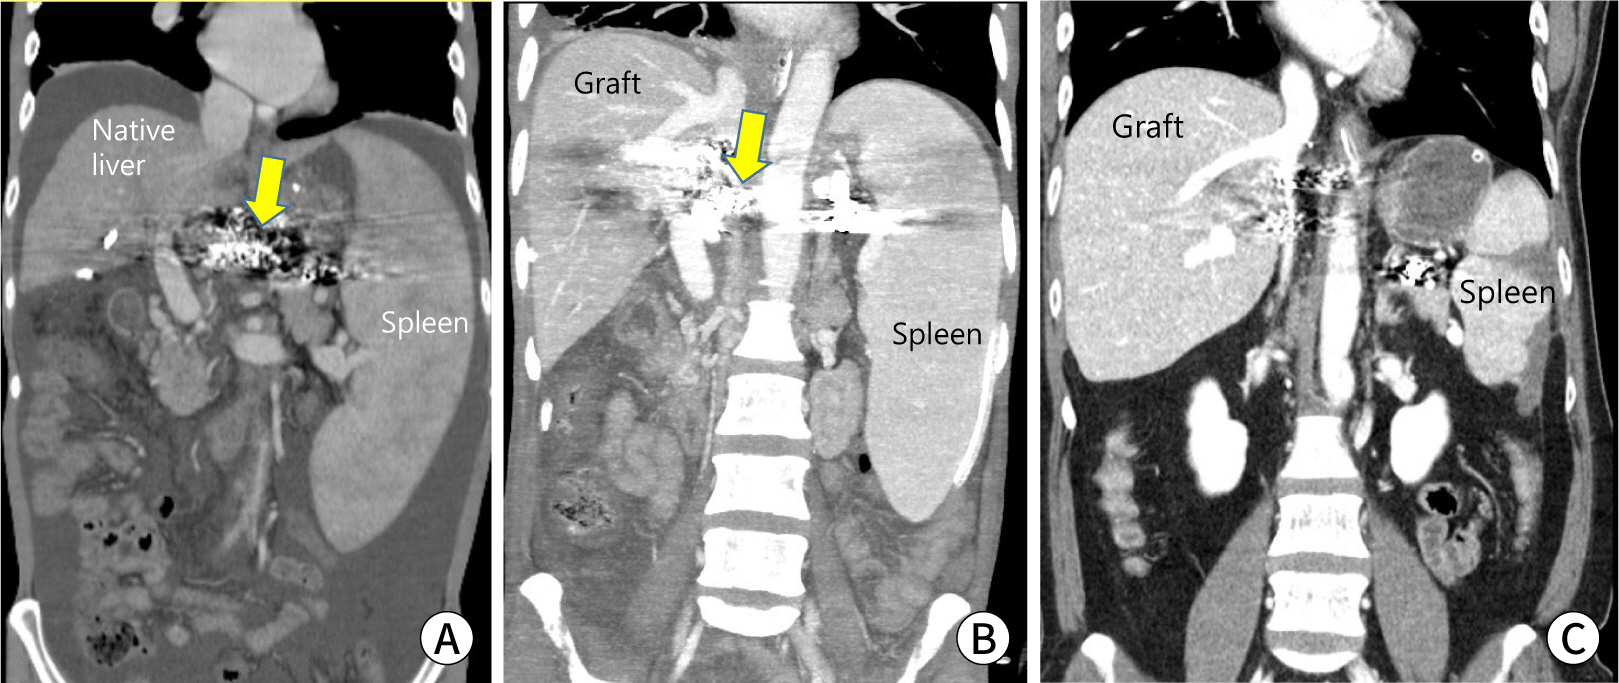

Fig. 2.

Auxiliary partial orthotopic liver transplantation to prevent the small-for-size syndrome. A 36-yr-old patient with Wilson’s disease has undergone living-donor liver transplantation from a 54-yr-old mother using a right posterior section graft. The graft-versus-recipient weight ratio is 0.64%. He has undergone a native liver hepatectomy 11 mo after transplantation. (A) A preoperative recipient computed tomography (CT) scan. (B) A CT scan of postoperative day 9. (C) A CT scan of postoperative 11 mo.

Regardless of these efforts during the operation, the SFSS can develop. Management goals include medical management of portal hypertension and graft support for acute liver failure. The medical reduction of portal pressure is similar to that of the pretransplant management of portal hypertension. Fluid balance and ascites control are basic concepts. Intervention radiology can play a role in splenic artery embolization by reducing portal pressure via flow reduction (Fig. 3).

Fig. 3.

Post-transplant splenic arterial embolization to reduce portal hypertension. A 40-yr-old woman with hepatitis B-related liver cirrhosis with the hepatorenal syndrome and uncontrolled ascites underwent living-donor liver transplantation from his 35-yr-old wife using a right liver graft. He underwent gastrorenal shunt occlusion before transplantation to control variceal bleeding and encephalopathy. One mo after transplantation, the patient underwent partial occlusion of the splenic artery because of uncontrolled ascites related to small-for-size syndrome (arrow, material for gastrorenal shunt occlusion). (A) A preoperative recipient computed tomography (CT) scan. (B) A CT scan of postoperative day 7. (C) A CT scan 2 yrs after transplantation.

Fig. 3. Post-transplant splenic arterial embolization to reduce portal hypertension. A 40-yr-old woman with hepatitis B-related liver cirrhosis with the hepatorenal syndrome and uncontrolled ascites underwent living-donor liver transplantation from his 35-yr-old wife using a right liver graft. He underwent gastrorenal shunt occlusion before transplantation to control variceal bleeding and encephalopathy. One mo after transplantation, the patient underwent partial occlusion of the splenic artery because of uncontrolled ascites related to small-for-size syndrome (arrow, material for gastrorenal shunt occlusion). (A) A preoperative recipient computed tomography (CT) scan. (B) A CT scan of postoperative day 7. (C) A CT scan 2 yrs after transplantation.